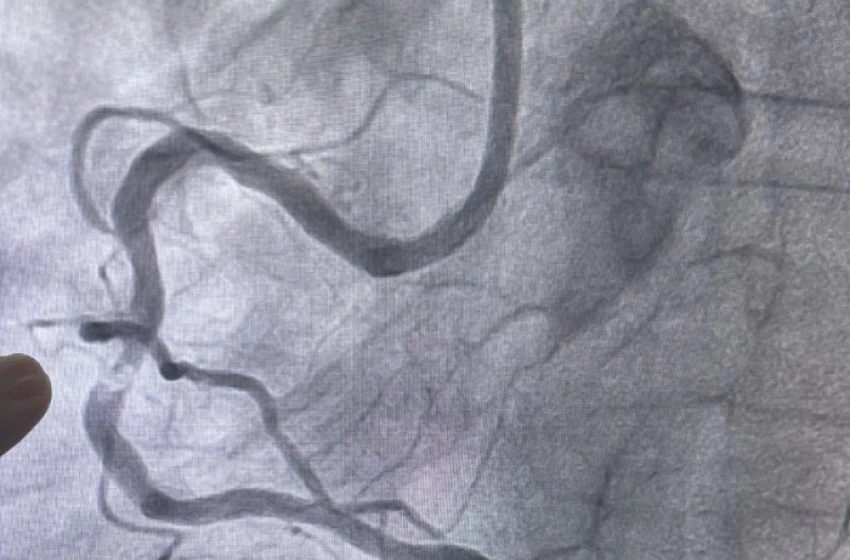

Realizado pelos cardiologistas intervencionistas Thiago Lisboa e Glauco Gusmão, o procedimento atendeu um paciente que apresentava dor torácica e falta de ar limitantes, com importante impacto na qualidade de vida. O cateterismo cardíaco evidenciou uma obstrução de 90% em uma artéria coronária, associada a uma placa extremamente calcificada (descrita como um verdadeiro "bloco de cálcio", conforme evidenciado nas imagens do exame), cenário em que as técnicas convencionais de angioplastia apresentam maior limitação técnica. Após o procedimento realizado com sucesso, o paciente recebeu alta hospitalar em menos de 24 horas.